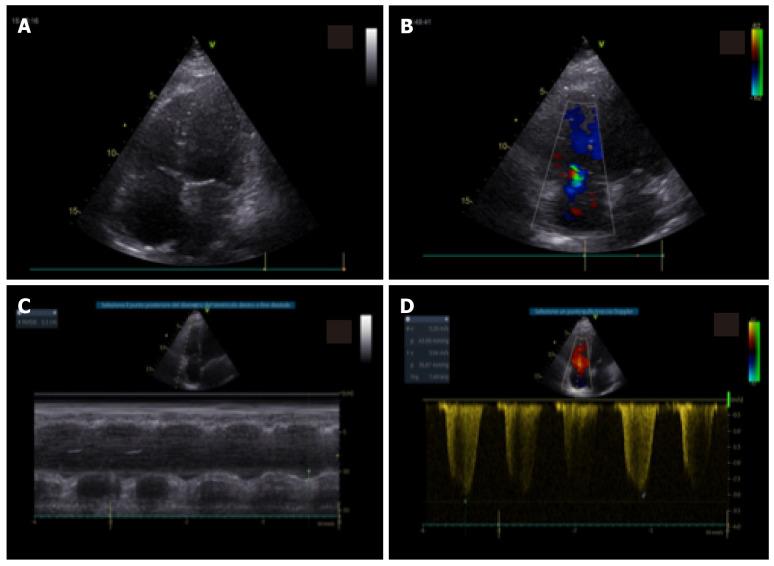

The integrated clinical, laboratory and ultrasound approach is essential for the diagnosis, evaluation and monitoring of the patient's therapy in coronavirus disease 2019 pneumonia. The ideal imaging approach in this context is not yet well defined. Chest X-ray is characterized by low sensitivity in identifying earlier lung changes. The "bedside" pulmonary ultrasound has an undeniable series of advantages in the patient at high infectious risk and can provide incremental data in the respiratory intensive care for the serial control of the individual patient as well as for the home delivery of the stabilized subjects. Pulmonary computed tomography shows high sensitivity but should not be routinely performed in all patients, because in the first 48 h it can be absolutely negative and in the late phase the imaging findings may not change the therapeutic approach. Echocardiography should be limited to patients with hemodynamic instability to assess ventricular function and pulmonary pressures.